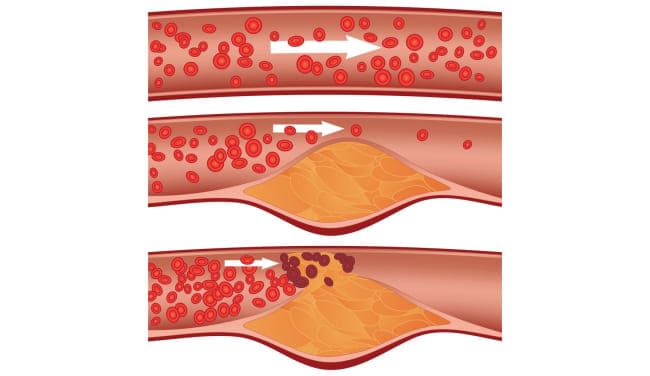

Todos saben que el colesterol es malo. Es él quien obstruye nuestros vasos sanguíneos, los estrecha e interrumpe la circulación sanguínea. Pero no es la única causa, ¿verdad?

Colesterol

Sí, tienes razón. Las placas de colesterol o "placas ateroscleróticas" representan aproximadamente el 65-70% de la contaminación vascular.

A los 50 años, hasta 5 kg de placas de colesterol se acumulan en los vasos de una persona. Estas placas estrechan el lumen de los vasos de 4 a 5 veces.

Imagínate. Si el lumen normal de un vaso es del tamaño de tu dedo, entonces 5 kg de placas de colesterol reducen el lumen al tamaño de 4 fósforos.

Las placas de colesterol por sí solas no son mortales. Sí, la calidad de vida disminuye, la presión arterial aumenta, hay dolores de cabeza y dolor en las articulaciones, debilidad y apatía. Mucho más peligrosas son las masas trombóticas y los cristales de calcio, que también se acumulan en nuestros vasos.